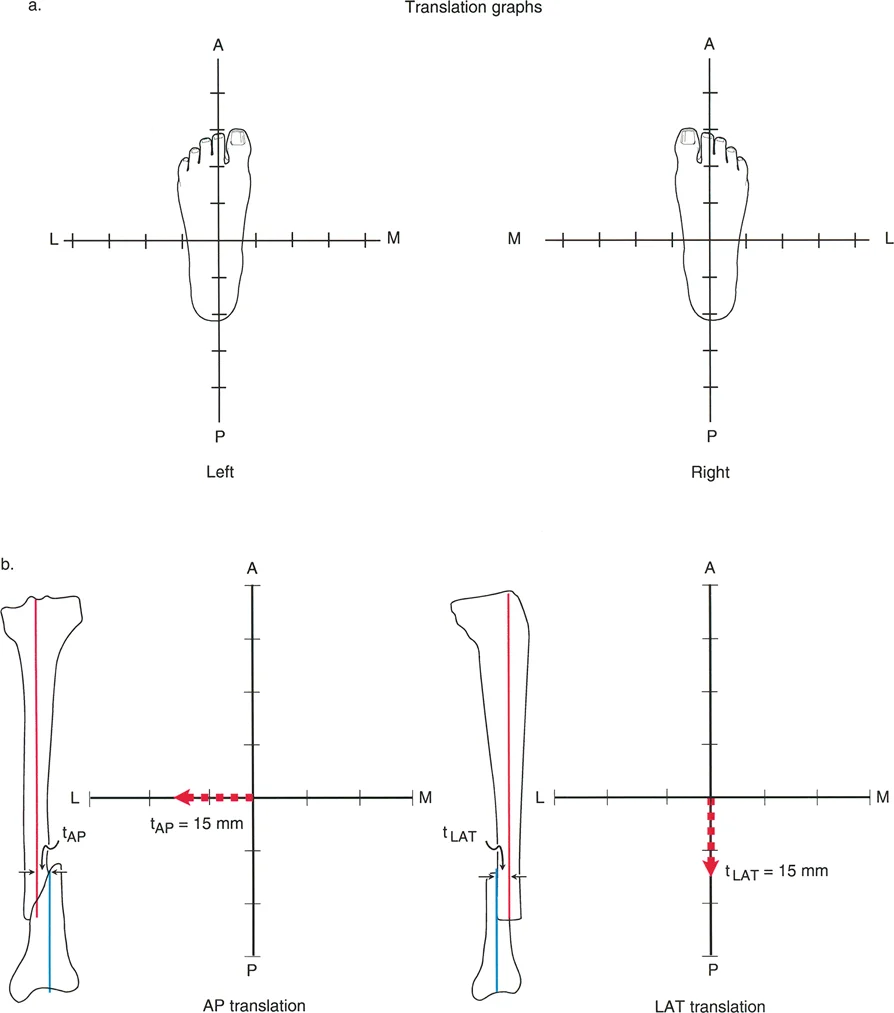

3. الرسوم البيانية للانزياح (Translation Graphs)

يستخدم الأستاذ الدكتور محمد هطيف رسوماً بيانية خاصة لتحليل تشوهات الانزياح، خاصة تلك التي تحدث في المستويات المائلة. هذه الرسوم البيانية تساعد في:

* تحديد الاتجاه الدقيق: مثل الاتجاه الأمامي-الخلفي (AP) أو الإنسي-الوحشي (LAT) أو مزيج منهما (Posterolateral - PL).

* قياس الحجم بدقة: تسمح بقياس حجم الانزياح بالمليمترات، حتى في المستويات المعقدة.

* تحديد مستوى الانزياح: المسافة من المفصل القريب إلى مستوى التداخل.